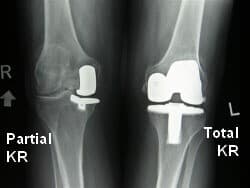

Зураг. Өвдөгний үе бүтэн болон дотор булууг хэсэгчлэн солих мэс засал.

Зураг. Мэс заслын дараах рентген зураг